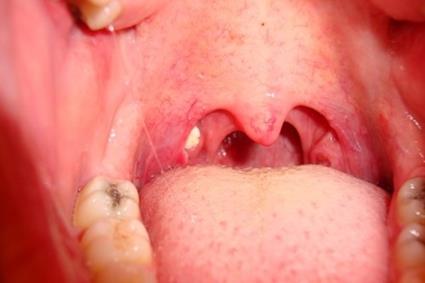

✅ 편도선의 붓기

결석이 생기면 편도선이 염증을 일으키고 붓기가 생길 수 있습니다. 이로 인해 목 부위에 불편함이나 통증이 발생할 수 있습니다.